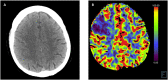

Arterial and venous thromboembolic disease in a patient with COVID-19: A case report